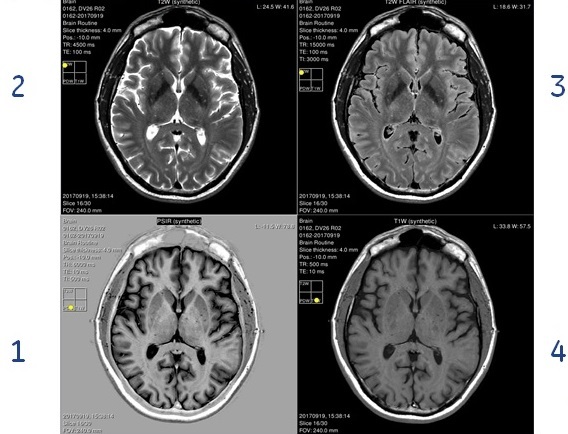

Figure 2. Example of synthetic images of an axial slice of the head, generated by MAGiC post-processing

Using the T1, T2, and PD maps, contrast-weighted T1, T2, T1 FLAIR, T2 FLAIR, STIR, PSIR and DIR images can be synthesized, at any desired combination of echo time TE, repetition time TR, and inversion delay times TI and TI2. The contrast-weighted image settings can be defined on the Add post process screen or from the MAGiC Session Application.